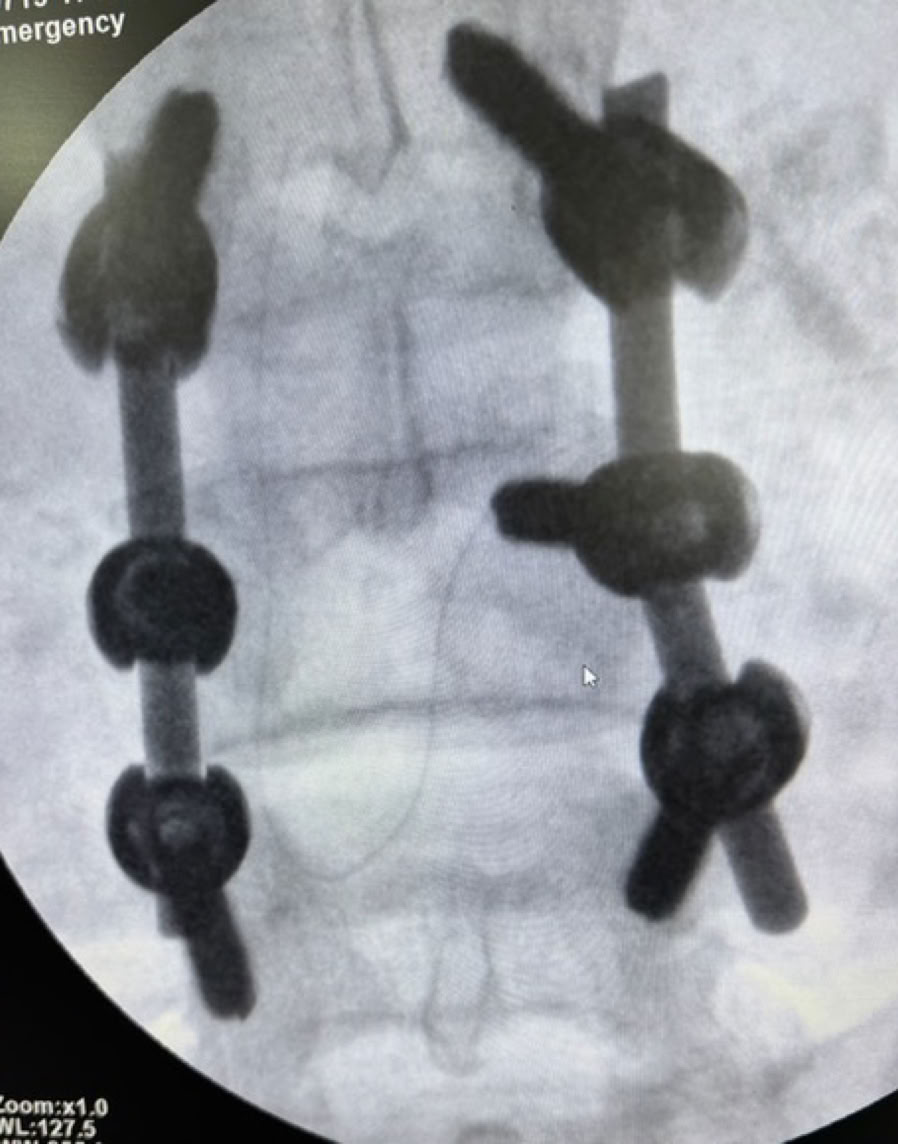

Nos encontramos dos casos de rodillas flotantes que pudimos resolver y casos de retardo de consolidación e infecciones de intervenciones previas. Igualmente las osteomielitis hematógenas y las sécales de la diabetes ocupa gran parte de la actividad de consultas de sala de curas y de las sesiones quirúrgicas.

A partir del lunes y tras la oración de bienvenida al inicio de la jornada en la que nos fuimos presentando todos los componentes de la expedición, las tareas asignadas se fueron distribuyendo entre la consulta, las dos salas de Curas y los dos quirófanos, que además se han mantenido activos todos los días de la semana en turnos de mañana y tarde con cirugías complejas en ambos. Esto nos ha permitido por ejemplo abordar principalmente enclavados de fémures y tibias y también casos de luxaciones inveteradas de hombro y de tobillo.